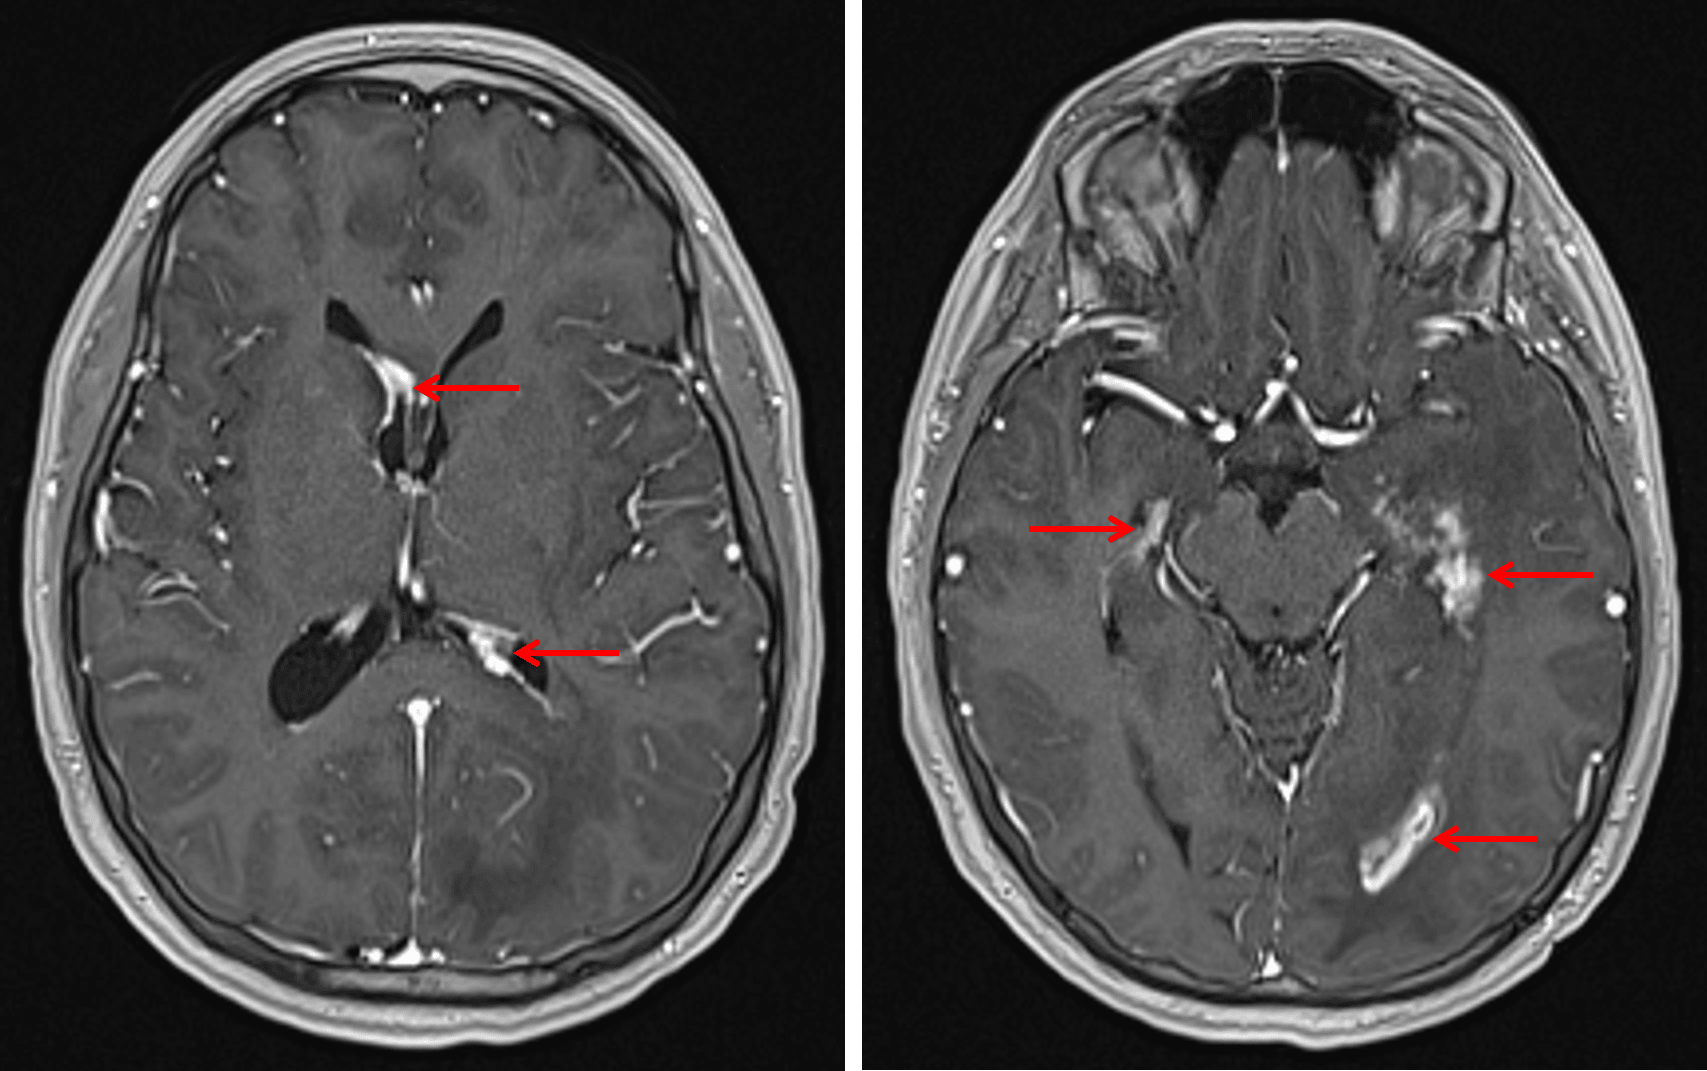

• Multifocal nodular enhancement along the ependymal lining of the ventricular system, most notably involving the atria, temporal horn, and occipital horn of the left lateral ventricle and the frontal and temporal horns of the right lateral ventricle

Multiple sites of nodular enhancement along the margins of the lateral ventricles (red arrows) in this patient with neurosarcoidosis.